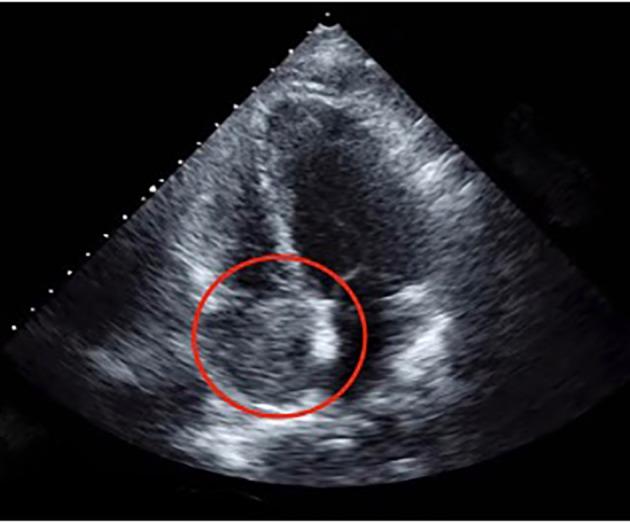

Colorectal cancers typically metastasize to the lymph nodes, liver or lungs. Metastasis to the heart is rare and although a few cases of cardiac metastases from colon cancer are described in the literature, cases of metastatic rectal cancer to the heart are far fewer. A 69-year-old woman with a history of rectal adenocarcinoma treated with neo-adjuvant chemotherapy and radiation, followed by resection and adjuvant chemotherapy, presented with increasing dyspnea on exertion and lower extremity edema 5 years after oncology follow-up. Echocardiography revealed a mass within the right atrium, which was biopsied and found to be consistent with metastatic rectal adenocarcinoma and a thrombus. The patient was deemed to be a poor surgical candidate given her co-morbidities and overall prognosis. Chemotherapy was offered and refused by the patient. The medical literature has a paucity of similar cases of rectal adenocarcinoma metastasizing to the right atrium. Further studies are needed to help guide standardized treatment options.

结直肠癌通常会转移至淋巴结、肝脏或肺部。转移至心脏较为罕见,尽管文献中描述了一些结肠癌心脏转移的病例,但直肠癌心脏转移的病例要少得多。一名69岁女性,有直肠腺癌病史,接受了新辅助化疗和放疗,随后进行了手术切除及辅助化疗,在肿瘤学随访5年后出现劳力性呼吸困难加重和下肢水肿。超声心动图显示右心房内有一肿块,经活检发现与转移性直肠腺癌及血栓相符。鉴于患者的合并症和总体预后,被认为不是手术的合适人选。提供了化疗方案,但患者拒绝。医学文献中关于直肠腺癌转移至右心房的类似病例较少。需要进一步研究以帮助指导标准化的治疗方案。